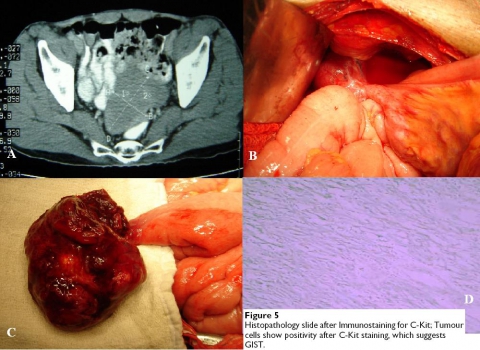

Gastrointestinal stromal tumor (GIST): chiếm khoảng 12%22, trên hình CT là mass mô mềm thường có hoại tử trung tâm và tăng quang viền.

Hình 34: GIST của túi thừa Meckel ởbệnh nhân nam 65 tuổi. A, CT thấy mass mô mềm ởvùng chậu nằm trên sau bàng quang và đè ép thành trước đại tràng sigma. B, U nằm trong túi thừa Meckel dính vào thành bàng quang. C,Túi thừa Meckel với phần u bịcắt rời. D,hình giải phẫu bệnh với chẩn đoán là GIST. (K Chandramohan et al (2007). Gastrointestinal stromal tumour inMeckel’s diverticulum. World Journal of Surgical Oncology; 5:50).